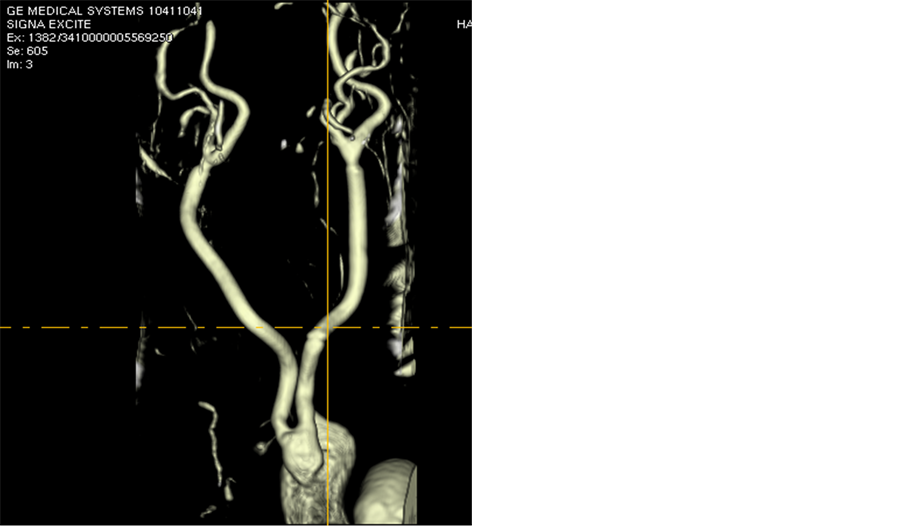

Figure 1. MRI examination visualizing the Aorto-Bi-Carotid (ABC) bypass. The graft is emerging off the ascending aorta and its limbs were anastomosed end-to-end to the distal com- mon carotid arteries.